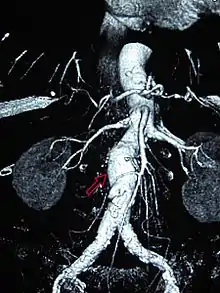

Abdominal aortic aneurysms (3,4 cm)

Abdominal aortic aneurysms (AAAs) are more common than their thoracic counterpart. One reason for this is that elastin, the principal load-bearing protein present in the wall of the aorta, is reduced in the abdominal aorta as compared to the thoracic aorta. Another is that the abdominal aorta does not possess vasa vasorum, the nutrient-supplying blood vessels within the wall of the aorta. Most AAA are true aneurysms that involve all three layers (tunica intima, tunica media and tunica adventitia). The prevalence of AAAs increases with age, with an average age of 65–70 at the time of diagnosis. AAAs have been attributed to atherosclerosis, though other factors are involved in their formation.[7]

CT reconstruction image of an abdominal aortic aneurysm